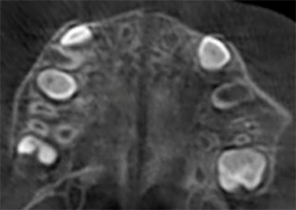

Opis przypadku nr 1

10 lat, 0 miesięcy, 18 etapów leczenia Invisalign Palatal Expander

Dzięki uprzejmości dr Sandry Khong Tai

Przed ekspansją eInvisalign Palatal Expander

Po ekspansji Invisalign Palatal Expander

Po leczeniu Invisalign First